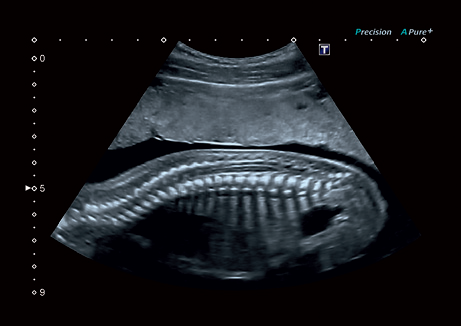

УЗИ-аппарат

Canon Aplio 300

Система Aplio 300 – идеальный вариант для тех, кому нужна надежная и эффективная работа оборудования в ежедневной практике. Эта высокопроизводительная, универсальная и экономичная система предлагает получение качественных изображений с впечатляющей глубиной и детализацией в самых разных областях медицины.

С данной моделью ультразвуковой системы специалист сможет легко создавать отчеты с информационными данными о прошлых исследованиях, вести базу данных, передавать ее на компьютер, вносить изменения и т.д. Aplio 300 всегда будет оставаться одним из лидеров продаж благодаря оптимальной стоимости, эргономичной платформе, мобильности и гарантии высокой эффективности работы.

• Превосходное качество визуализации и детализации анатомических структур для широкого спектра областей использования.

Режимы визуализации Canon (Toshiba) Aplio 300

B, M, PWD, CWD, ЦДК, THI, 4D, динамический поток (Dynamic Flow), энергетический доплер (Power), контрастная эхография (CHI 2D) и комбинированные режимы, включая следующие: B/M, B/PWD, BDF/PDW, BDF/MDF,BDF/MDF/PWD, 2D/CWD, BDF/CWD (BDF-режим изображения, в котором CFM изображение накладывается на B-режим изображения, MDF-режим изображения, в котором CFM изображение накладывается на M-режим изображения)

• Precision Imaging - технология получения изображений мелких деталей с четко очерченными границами и высокой однородностью